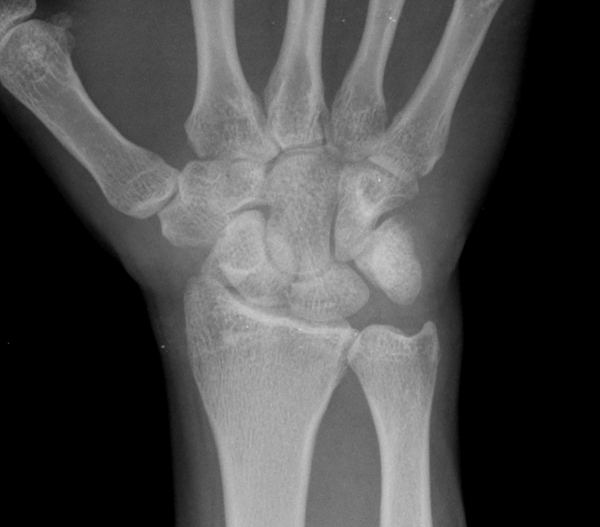

¹æ»ç¼± °Ë»ç : ¼Õ¸ñ Ãø¸é »çÁø¿¡¼­ ¿ù»ó°ñ ÀåÃø¿¡¼­ °ñ±ØÀÌ °üÂûµÊ( »çÁø 4).